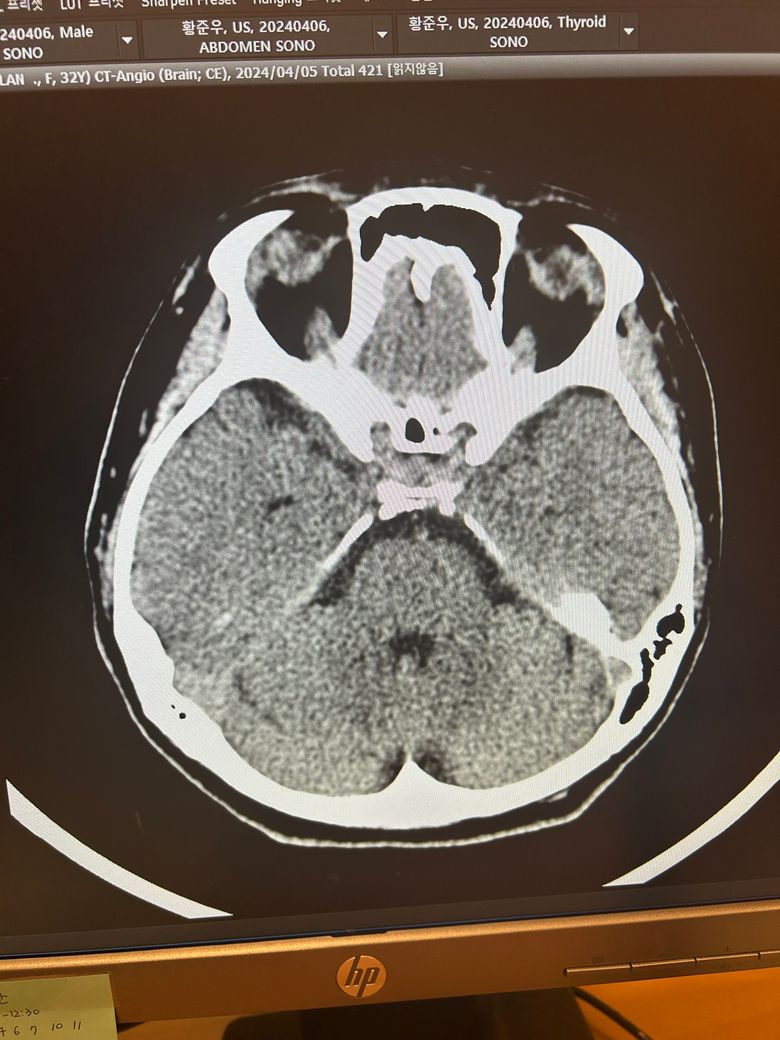

두통과 목뻐근함이 일주일째 심해서 뇌ct검사를 했습니다.

영상은 이렇게 보이는데 어떻게 의심되시나요?

석회화랑 다른것도 보이시나요?